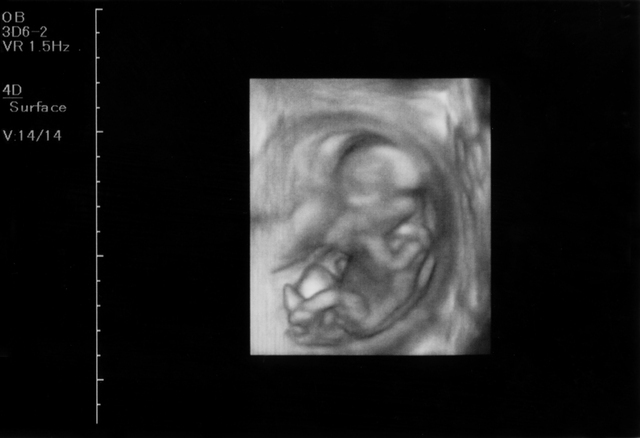

妊娠4ヶ月の胎児の大きさ、状態

13週ころには内臓や手足などの器官はほぼ完成し、機能も発達します。細かい動きもみられるようになります。

羊水を飲み込み排泄したり、手足もよく動かしたりするようになります。指を口でしゃぶるような様子を見せることもあります。まだまだ小さい赤ちゃんですが、もうすでに外での生活に向けて練習を始めているんですね。